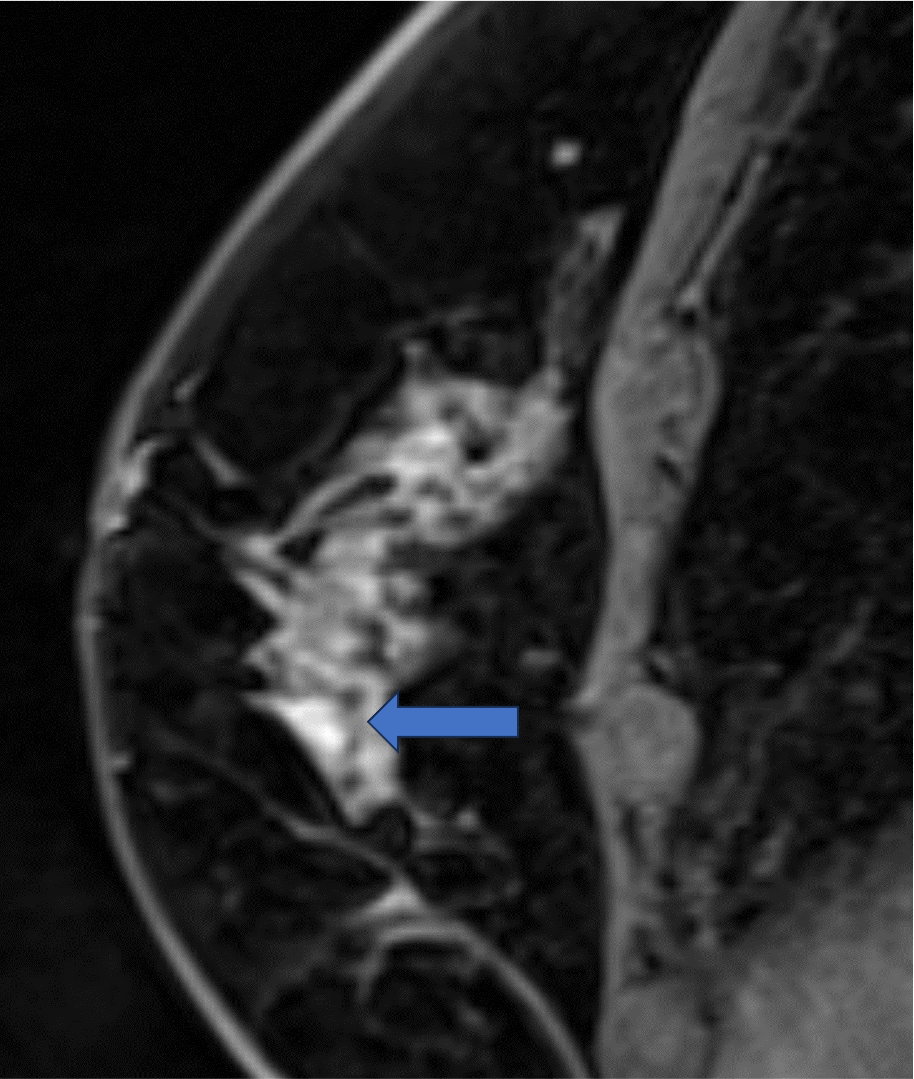

6. 造影後高分解能画像

病変は扁平な形状で内部にはdark internal septation様の構造が見られる。